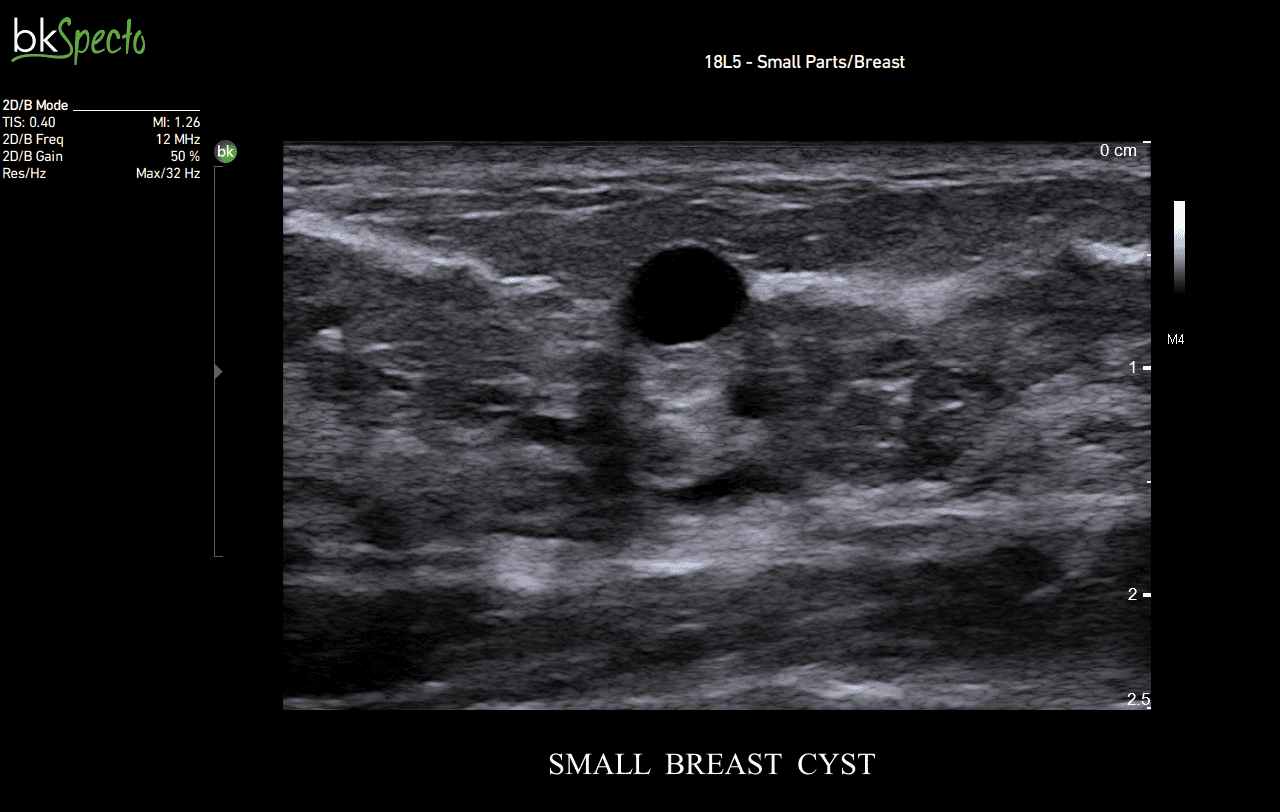

BkSpecto là hệ thống siêu âm chuyên về các thủ thuật can thiệp cho các chuyên khoa: Tiết niệu, gây mê, cơ, tuyến vú, tuyến giáp, sản phụ khoa và hậu môn trực tràng.